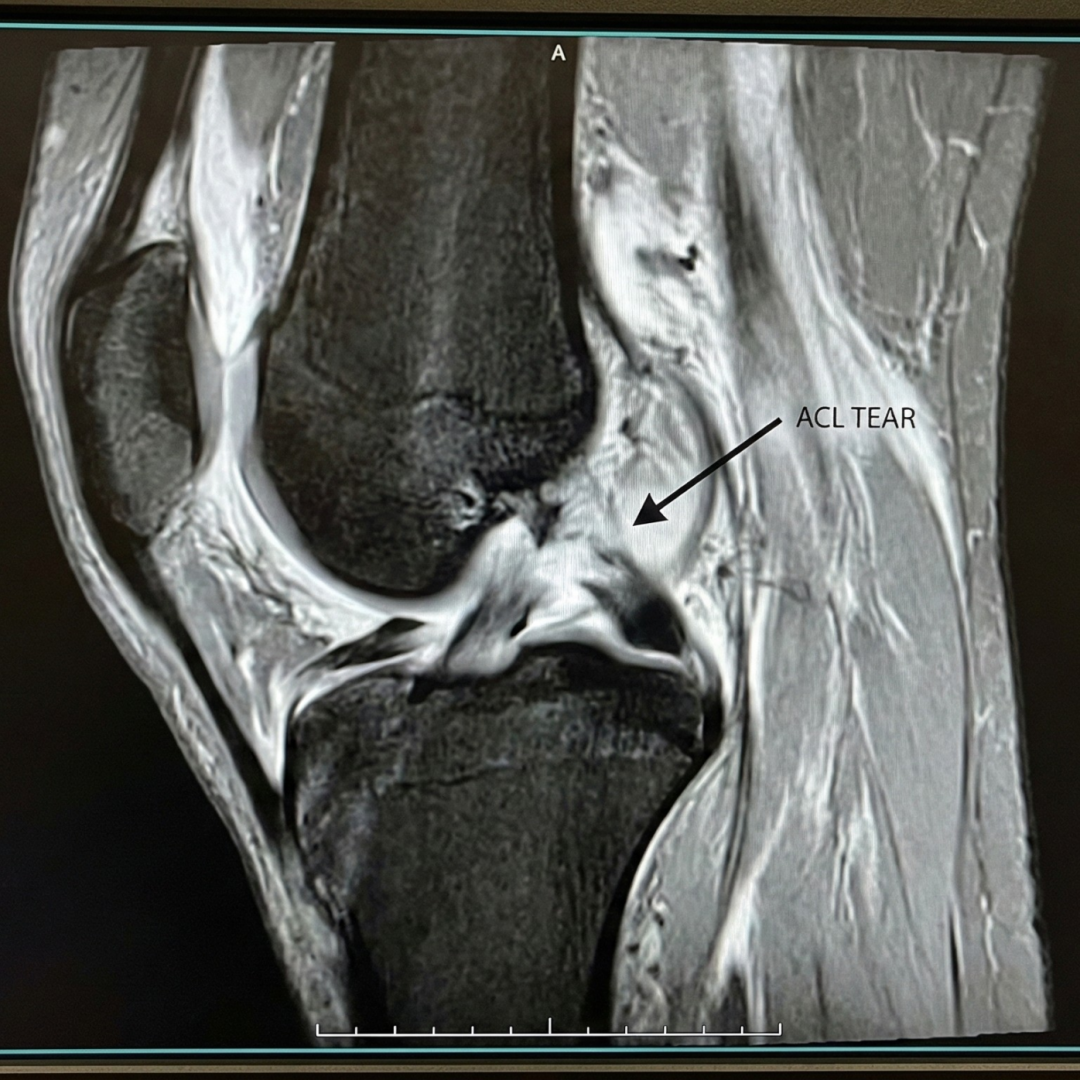

Diagnosis is confirmed with MRI which tells about the extent injury. The extent of injury helps us to formulate strategy regarding the correct line of treatment.